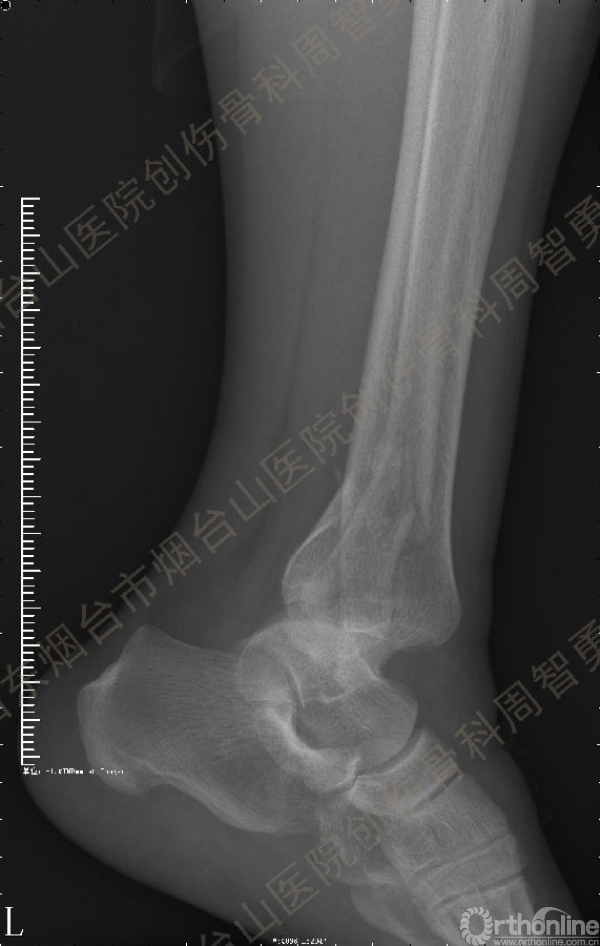

患者一般情况可,左踝关节肿胀,见皮下瘀斑,内、外、后侧有压痛,左踝关节主动运动受限,左足皮肤感觉、血供未见明显异常,左足趾各关节可主动运动。左踝关节正位X线片和CT重建示内踝内上方双层骨皮质影(图1a,c),CT示后侧骨折块分为后内侧骨折块和后外侧骨折块(图2a,b),后内侧骨折块累及内踝后丘,后丘骨折线呈冠状位(图2c),后内侧骨折块腹侧有向近端塌陷的小块骨软骨骨折块(图2d),CT也显示Chaput骨折块(图1c,2e)。

经典的后踝骨折发生于低能量旋转外力所致的踝关节骨折;标准pilon骨折见于高能量轴向暴力;而后侧pilon骨折是旋转外力和轴向暴力共同作用的结果,属于中等能量的损伤。踝关节骨折中的后踝骨折源自下胫腓后韧带的牵拉,骨折块位于后外侧,常为单一的三角形骨折块,大小从关节外片状骨折到累及胫骨远端关节面矢状径的40%(图4a)。后侧pilon骨折中的后侧骨折块较大,累及内踝后丘(三角韧带深层起点)在内的整个胫骨远端后侧,分为后内侧骨折块和后外侧骨折块,后内侧骨折块腹侧有向近端塌陷的骨软骨骨折块(图4b)。后侧pilon骨折中的内踝骨折线并不是水平位而是冠状位,可合并内踝前丘骨折。后侧pilon骨折踝关节正位X线片示特异性的内踝内上方双层骨皮质影(图1a,c)。这是由于后内侧骨折块的骨折线延伸到胫骨远端骨骺和干骺端的内侧骨皮质,其移位后的边缘成像所致。水平位CT显示后侧骨折块分为后内侧骨折块和后外侧骨折块,矢状位CT示后内侧骨折块腹侧有向近端塌陷的骨软骨骨折块。

③影像表现:踝关节正位X片显示特异性的内踝内上方双层骨皮质影

↑图 1a

图 1 术前左踝关节正侧位X线片和CT重建,箭头所示内踝内上方双层骨皮质影(a,c)